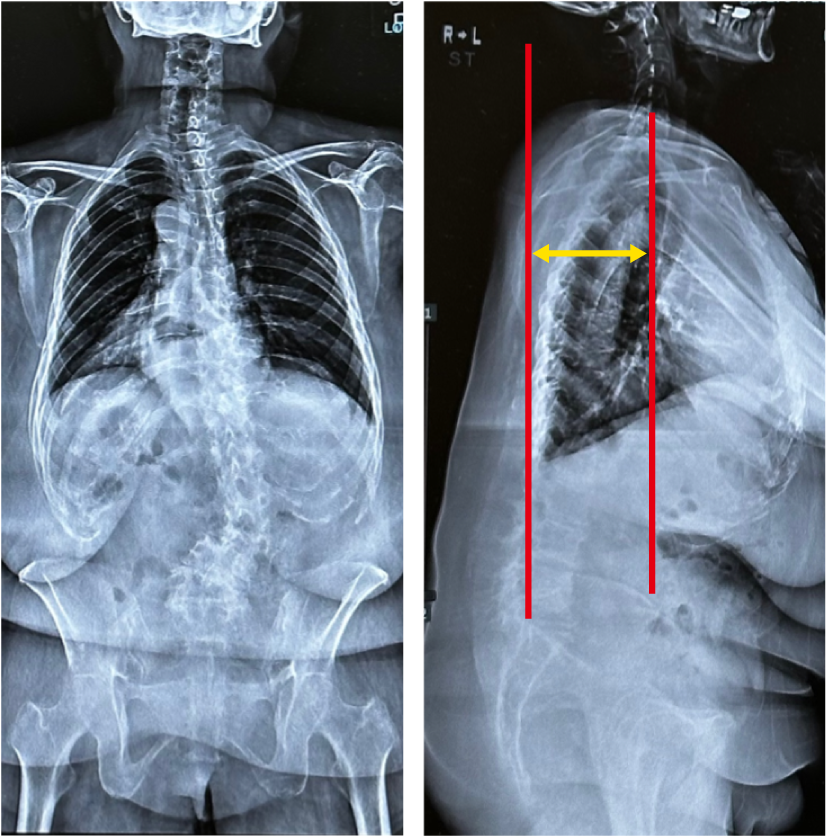

長年の放置により変形が進行した特発性側弯症の立位全脊柱X線正面像

特発性側弯症は、思春期には痛みなどの自覚症状を伴わない場合が多いが、変形を放置すると、大きなカーブの場合(特に50°以上)は年々進行し、変形や加齢性変化が加わり重大な機能障害を招くことがある。